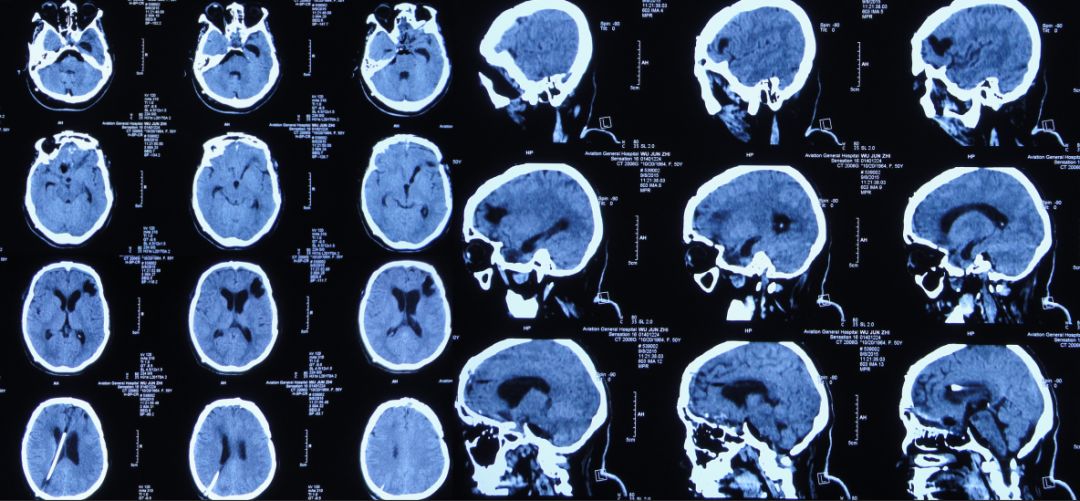

患者女,50岁,安徽省淮北市人。2014年12月14日,患者因高处坠落伤(2米左右)伤及头胸部及四肢,致昏迷,左耳、左鼻流血性液体,急诊前往安徽省淮南市潘集区某医院急查头CT显示左额叶脑挫伤、左侧颞骨凹陷性骨折、脑肿胀、颅内积气(图1);眼眶CT显示双侧眼眶内侧壁骨折(图2);胸部CT显示左侧肋骨骨折伴肺挫伤;右上肢X片显示右桡骨远端粉碎性骨折;左肩部X片显示左侧锁骨骨折。立即给予住院,保守治疗。

图2:2014年12月14日眼眶CT:双侧眼眶内侧壁骨折